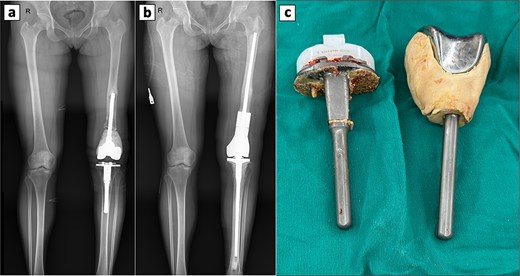

Four years earlier, she had a pathologic distal femur fracture after a minor fall. Radiographs showed a comminuted metaphyseal fracture with an expansile lytic lesion across both condyles to the articular surfaces, cortical thinning, periosteal lift, and soft-tissue haze (Fig. 1a and b). A ten-year history of dull knee pain implied a chronic lesion with subchondral erosion, leaving no base for fixation or joint salvage. Thus, intralesional curettage and osteosynthesis carried high risks of mechanical failure and local recurrence, especially with articular breach and extensive bone loss. Conversely, segmental resection with primary cemented endoprosthetic TKA allowed en bloc removal, immediate restoration of alignment and congruity, and early full weight-bearing; the stemmed construct bypassed the compromised metaphysis. The patient therefore underwent complete excision of the distal femur and lesion with cemented TKA, achieving a stable reconstruction (Fig. 1c–f). Histology and Immunohistochemistry (IHC) confirmed a GCT composed of multinucleated giant cells and mononuclear stromal cells, supporting the oncologic choice of resection arthroplasty (Fig. 2a–g).

Radiographic and intraoperative findings in primary total knee arthroplasty. Preoperative anteroposterior (a) and lateral (b) radiograph of the knee showing a GCT with an associated fracture in the distal femur. Postoperative anteroposterior (c) and lateral (d) radiograph of the knee following primary total knee replacement. (e) Complete resection of the distal femur. (d) Gross specimens of the distal femur.